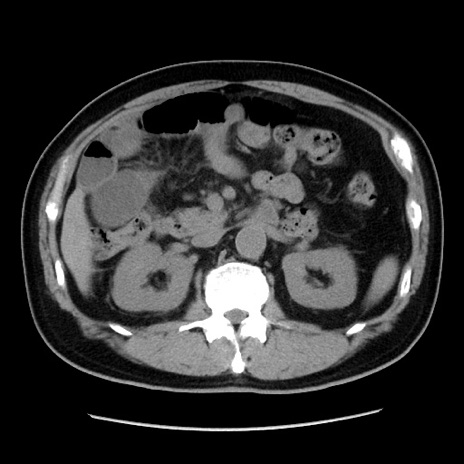

症例16(横断像)

【症例】 70歳代男性

【主訴】 腹痛、嘔吐

【現病歴】 約1ヶ月前より間欠的に腹痛と嘔吐あり、当院消化器内科を受診したところCTで多発する肝臓のLDAを指摘され、精査中であった。以降は消化器症状は安定していたが、2日前より嘔気と腹痛があり、同日より排便・排ガスが消失した。改善認めず、 本日、救急外来を受診した。

【既往歴】 大腸ポリープ切除後。

【身体所見】意識清明・会話良好、BT 36.3℃、BP 127/80mmHg、 P 80bpm、腹部:膨満あり、平坦・軟、上腹部正中および下腹部正中に圧痛あり、反跳痛なし、筋性防御なし。

【データ】WBC 7200、CRP 0.77